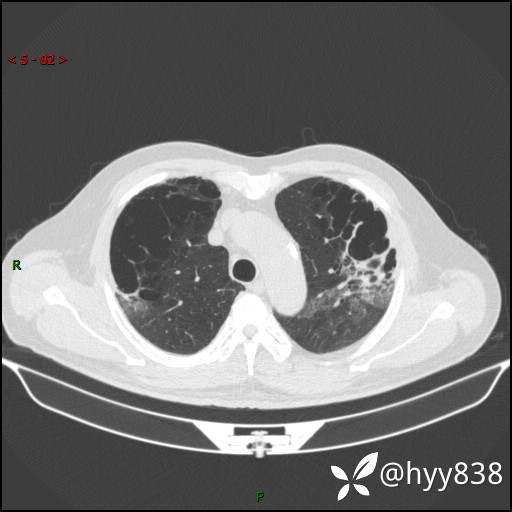

一周后胸部CT